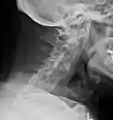

Lateral X-ray of the mid back in ankylosing spondylitis

Lateral X-ray of the neck in ankylosing spondylitis

The earliest changes demonstrable by plain X-ray shows erosions and sclerosis in sacroiliac joints. Progression of the erosions leads to widening of the joint space and bony sclerosis. X-ray spine can reveal squaring of vertebrae with bony spur formation called syndesmophyte. This causes the bamboo spine appearance. A drawback of X-ray diagnosis is the signs and symptoms of AS have usually been established as long as 7–10 years prior to X-ray-evident changes occurring on a plain film X-ray, which means a delay of as long as 10 years before adequate therapies can be introduced.[24]